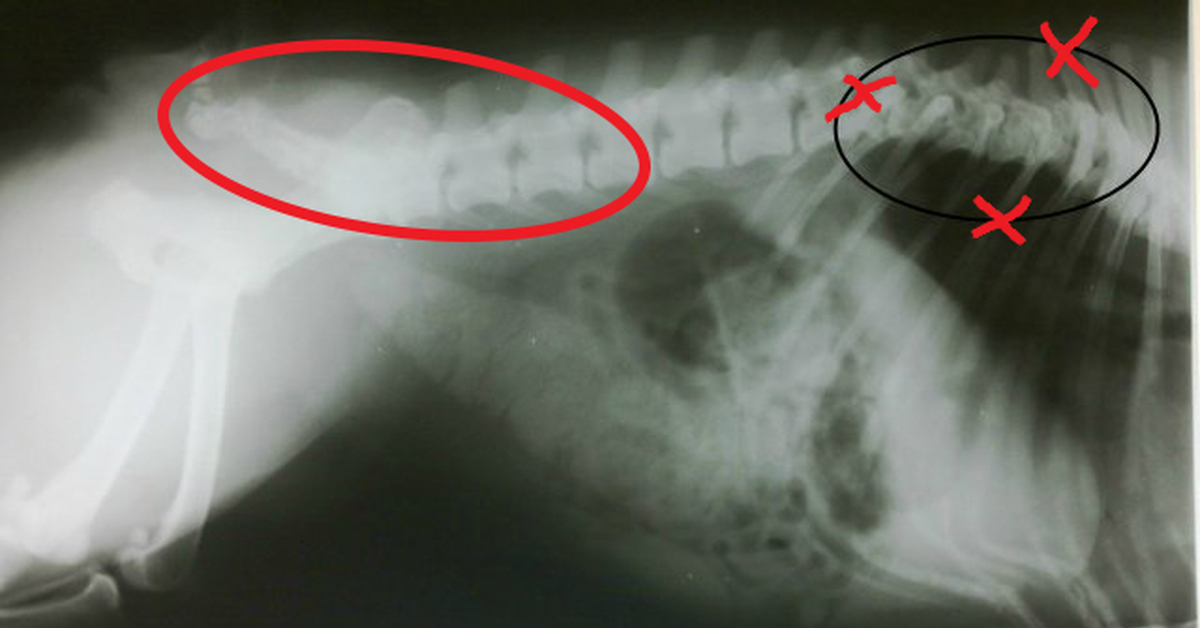

Заболевания позвоночника у домашних животных: диагностика и лечение

Раздел: Визуальные истории